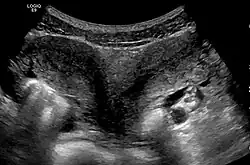

- The two Müllerian ducts have fused, but the partition between them is still present, splitting the system into two parts. With a complete septum the vagina, cervix and the uterus can be partitioned. Usually the septum affects only the cranial part of the uterus. A uterine septum is the most common uterine malformation and a cause for miscarriages. It is diagnosed by medical image techniques, i.e. ultrasound or an MRI. MRI is considered the preferred modality due to its multiplanar capabilities as well as its ability to evaluate the uterine contour, junctional zone, and other pelvic anatomy. A hysterosalpingogram is not considered as useful due to the inability of the technique to evaluate the exterior contour of the uterus and distinguish between a bicornuate and septate uterus. This condition can be complete or partial

Diagnosis

Besides a physical examination, the physician will need imaging techniques to determine the character of the malformation: gynecologic ultrasonography, pelvic MRI, or hysterosalpingography. A hysterosalpingogram is not considered as useful due to the inability of the technique to evaluate the exterior contour of the uterus and distinguish between a bicornuate and septate uterus. In addition, laparoscopy and/or hysteroscopy may be indicated. In some patients the vaginal development may be affected.